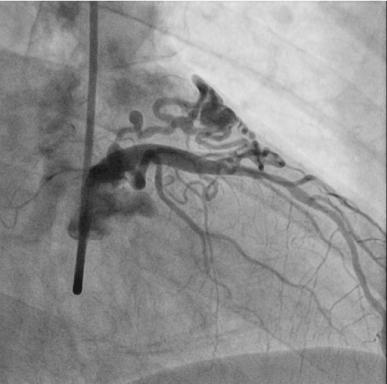

A 59-year-old man presented to the outpatient clinic of cardiology department with recurrent chest pain for several weeks. An electrocardiogram showed sinus rhythm with T wave inversion in leads V2 through V6, and appearance suggestive of anterior-wall ischemia (Figure 1). Two-dimensional transthoracic echocardiography showed no regional wall motion abnormality. Elective coronary angiography was performed. Very tortuous and dilated fistula track originated from left main stem linked to ‘heart-shaped’ small chamber and drained to right atrium on various projection views (Figures 2-4). He was referred for surgical obliteration of the fistula. After surgery, he suffered from postoperative myocardial infarction and heart failure. With ongoing medical conservative treatment, the chest pain and dyspnea resolved within 2 weeks, respectively and discharged. He was discovered with state of death in his home at follow-up 3 months later. The cause of death is not known but suggestive of sudden cardiac death. Perioperative myocardial infarction is an important complication of ligation of coronary artery fistula and could contribute to his sudden death.

Figure 2. Coronary angiogram with AP caudal view